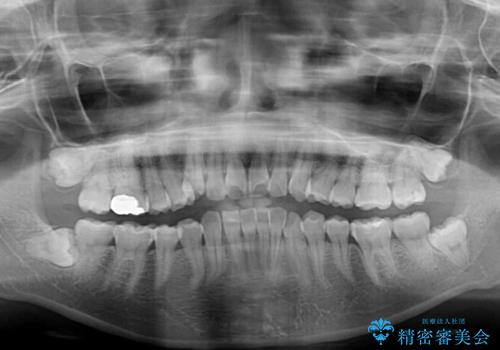

- 上下前歯のデコボコを改善したいとのことで来院された患者様です。

マウスピースを長時間装着し続ける自信はあまりないとのことでしたが、目立たない装置であれば頑張って装着するとのことで、インビザラインによる矯正治療を行うこととしました。

初めの1年くらいは何とか頑張って装着してくださいましたが、途中から変化をあまり感じられなくなり、日々の装着時間は徐々に短くなってしまいました。

前歯のデコボコはもっと改善できましたが、3年半が経過し、初診時と比べたら大幅に良くなったとのことで終了することとなりました。